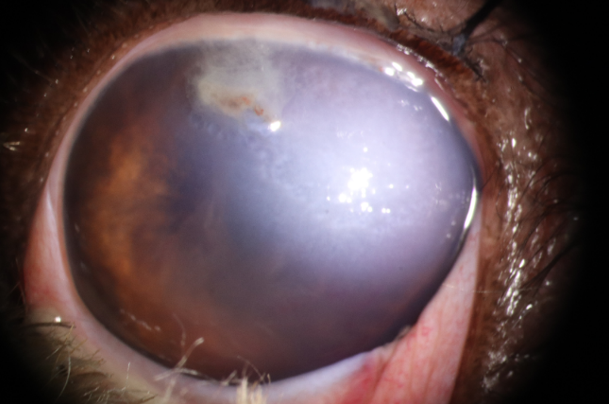

세극등 현미경 검사상 결막하 출혈, 얕거나 평평한 전방안방, 매우 깊은 전방안방, 뾰족한 동공, 각막 또는 공막 단절, 전방출혈, 홍채 변형, 포도막 탈출, 수정체 파열, 유리체 출혈, 망막 열공 또는 망막 출혈과 같은 후방 안구 소견은 외상이 의심되는 환자에게서 관찰될 경우 회복에 우려될 수 있는 증상입니다.

.png)

사진 1. 고양이 발톱에 의한 penetrating injury. 결막의 중등도의 충혈 및 부종 확인되며, 천공부위는 fibrin으로 일시적으로 막힘. 천공 부위 주변부 각막의 부종 확인됨. 전안방은 fibrin 및 출혈괴 확인됨. 안방수의 흐림정도는 매우 심하였으며, 홍채는 각막 열린 부분으로 부분 전방 유착 확인됨.